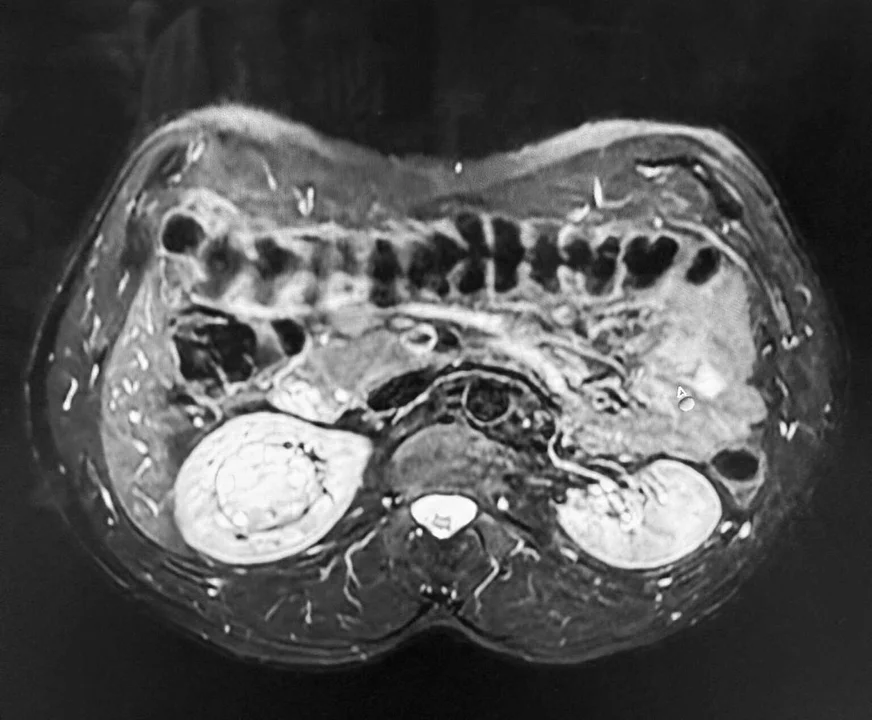

Guz był w najtrudniejszym możliwym miejscu, a ryzyko bardzo wysokie.